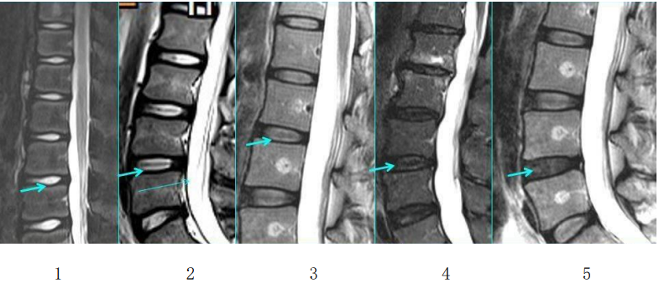

来!带你快速了解腰椎间盘突出症

来!带你快速了解腰椎间盘突出症来!带你快速了解腰椎间盘突出症01什么是腰椎间盘突出症(简称腰脱症)?腰椎间盘就像轮胎,外面一层是韧性较强的外胎,里面包裹着韧性较弱的内胎,均具有一定的弹性,可以缓冲吸收相邻椎体之间的压力。正常情况下,椎…51吃瓜网详情 +